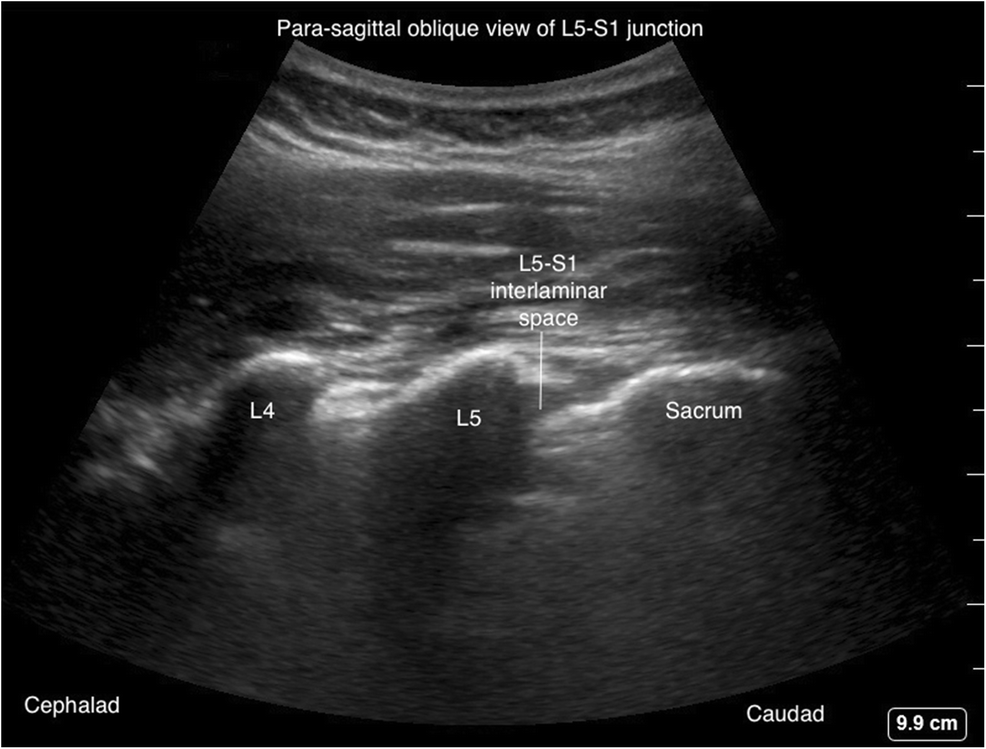

Датчик помещается над крестцом для идентификации поперечного отростка L5 и межпозвонкового промежутка L5-S1 (рис. 8 и 9).

Затем датчик сдвигают краниально для определения соответствующих промежутков L5–L4, L4–L3 и L3–L2.

Рис. Парасагиттальный вид крестцово-нижнепоясничных позвонков.

Рис. Парасагиттальный косой вид межламинарного пространства L5-S1.